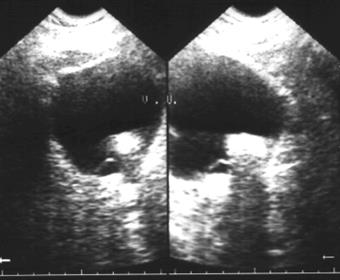

| Рис. 6.17. Сонограмма вдоль длинной оси правой почки. Карбункулы почки в виде гипоэхогенных зон с нечеткими контурами (стрелки). |

Рис. 6.18. Компьютерная томограмма брюшной полости на уровне L2. Левая почка деформирована с наличием псевдокистозных образований. Правая почка в норме. Абсцесс левой почки. | Рис. 6.19. Компьютерная томограмма брюшной полости на уровне L3. То же наблюдение, что и на предыдущей компьютерной томограмме. Определяется распространение абсцесса левой почки книзу в парааортальной области слева в виде объемного образования неоднородной плотности. |